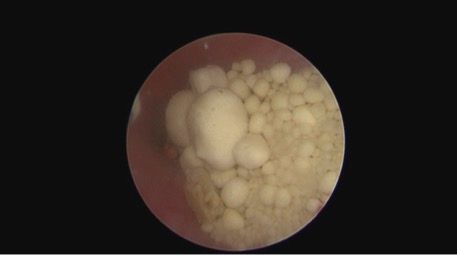

For this technique, an approximately 2-cm ventral midline incision is made following placement of a large urinary catheter, and an Alexis wound retractor is placed to provide radial retraction. A stay suture is placed in the apex of the bladder, and then 2 additional stay sutures are placed, forming a triangle. A stab incision is made in the center of the triangle using an No. 11 blade, and a 5-mm laparoscopic point is inserted into the cystotomy. At this point, the endoscope can be introduced and fluids connected to the urinary catheter. Calculi will generally accumulate toward the trigone and can be visualized with the endoscope (Figure 1). Small stones can be flushed through the laparoscopic port and collected, but larger ones will need to be manipulated with the stone extractor basket to be removed.